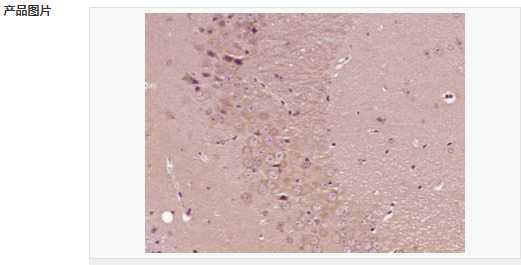

交叉反應:Mouse,Rat(predicted:Human,Pig) 推薦應用:IHC-P,IHC-F,IF,ELISA

| 產品應用 | ELISA=1:5000-10000 IHC-P=1:100-500 IHC-F=1:100-500 IF=1:100-500 (石蠟切片需做抗原修復) not yet tested in other applications. optimal dilutions/concentrations should be determined by the end user. |